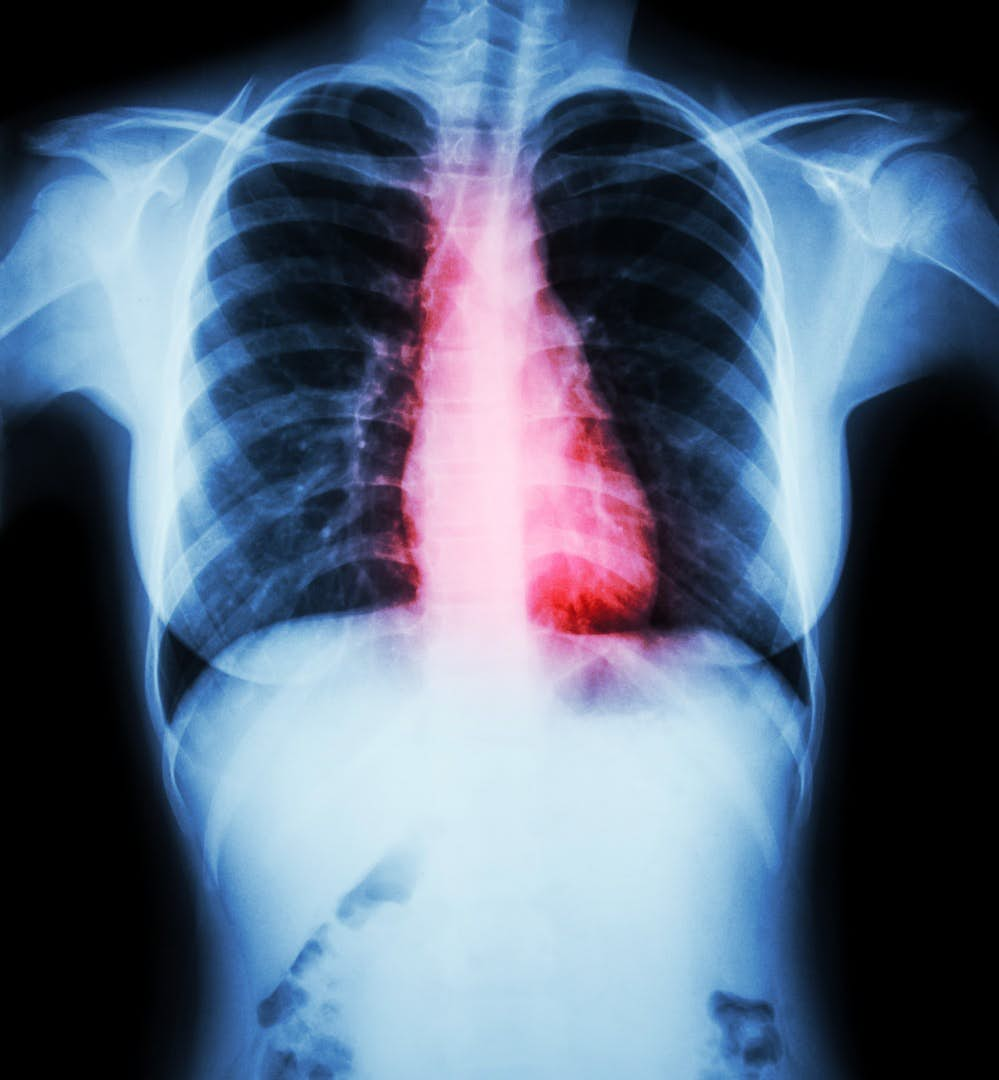

Hasarlı kalplerin tedavisi

Geçtiğimiz yıl, Japon hükümeti, İPKH’lern milyonlarca kalp kası hücresi içeren tabakalar oluşturmak için kullanıldığı ve daha sonra kalp hastalığı olan hastaların kalplerine aşılandığı insanlar üzerinde bir türden ilk denemeyi onayladı.

Onayın nedeni ; domuzlarda yapılan deneylerin başarı ile sonuçlanması.

Onaydan sonra üç hasta üzerinde yapılan denemelerde başarılı oldu, şimdi hedef 10 hastayı kapsayan daha büyük bir deneme. Eğer bu deneme de başarılı olursa bu teknik hayata geçebilecek.